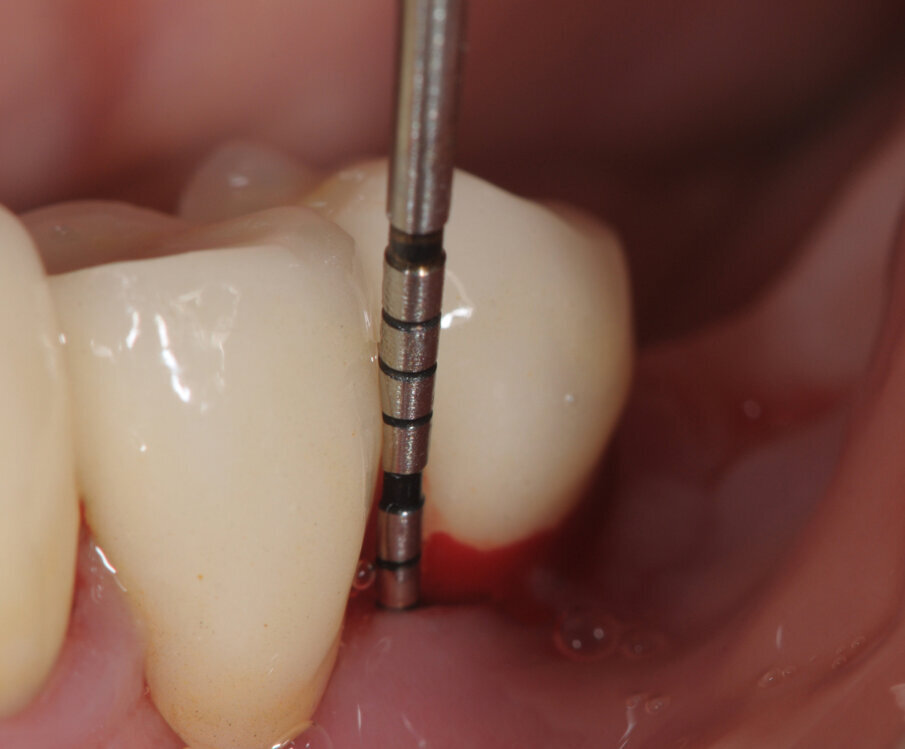

La paziente viene sottoposta alla medesima seduta fatta nei primi 15 giorni con variazione nella frequenza portata ad 1 applicazione per settimana (Figg. 1-6).

A termine del trattamento descritto in precedenza da un punto di vista clinico abbiamo ottenuto un ripristino dei parametri di salute dell’impianto ovvero la scomparsa del sanguinamento dell’edema e della purulenza, in oltre si è verificata una riepitelizzazione dei tessuti molli limitrofi l’impianto. Da un punto di vista radiografico abbiamo ottenuto la neoformazione di osso attorno alle spire dell’impianto (con relativo aumento della stabilità) che a inizio terapia era da considerarsi potenzialmente come perso. La radiografia a 60 gg prima ed a 1 anno mostrano quanto prima descritto, ovvero un ripopolamento di componenti cellulari ossei sull’impianto con un recupero di 3 spire implantari (Figg. 7-9).